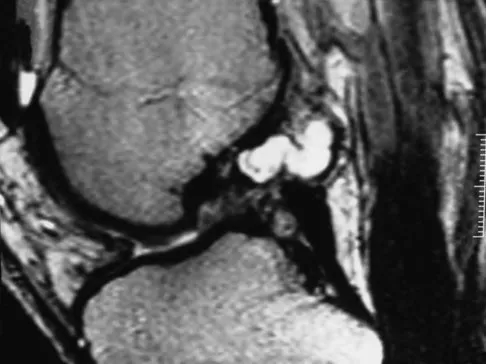

Question 23

A 39-year-old competitive cyclist sustains an injury to her left hip in a fall. Gadolinium arthrography, with an accompanying MRI scan, is shown in Figure 31. A cleft, or defect, identified by the arrow, indicates a detachment of the

Explanation